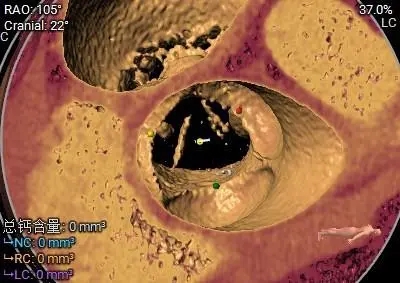

三叶瓣重度钙化

-

敞口流出道

钙化主要分布于左、无瓣叶上

STJ及升主未见明显扩张

冠脉风险评估

Left Coronary 8.0mm

Right Coronary 18.7mm

Left Ventricular

左冠开口较低,结合瓦氏窦大小,预估冠脉风险相对较低